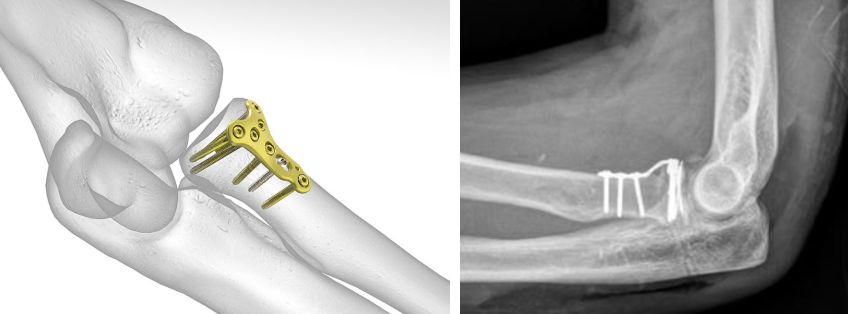

관혈적 정복 및 내고정술(ORIF): 골절 부위를 직접 노출해 맞추고 금속판, 나사 등으로 고정

요골두 절제 및 인공관절 치환술 : 골절 부위가 심하게 부서진 경우